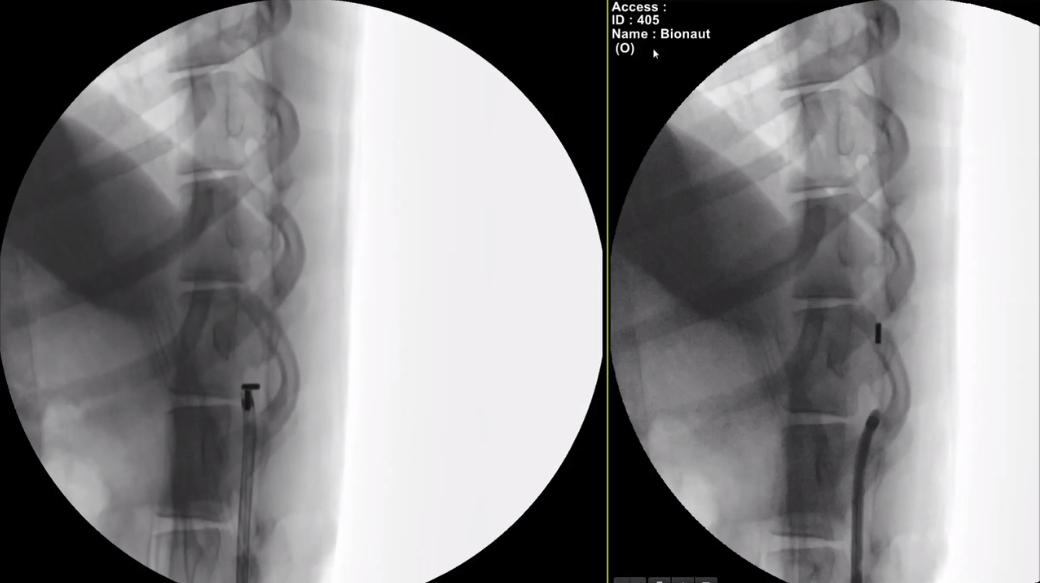

具体而言,该公司会在其首次临床试验中把装载着治疗药物的微型机器人注射到脊柱中,并使用一组位于头部和颈部周围的磁铁产生的磁场将机器人引导进入脑部患病区域。在到达正确的位置后,另一个磁信号将激活机器人药物舱的开关,释放药物。药物卸载后,医生再引导机器人返回至起始点,将其从脊柱处接离。

图 | Bionaut 微型机器人进入活羊的蛛网膜下腔(来源:Bionaut Labs 官网)

Shpigelmacher 进一步解释道,目前的技术已经允许机器人制造得足够小,但为了确保其能够在 X 光下实时清晰可见、方便追踪和操控,Bionaut 将微型机器人的大小尽可能保持在 1 毫米左右。